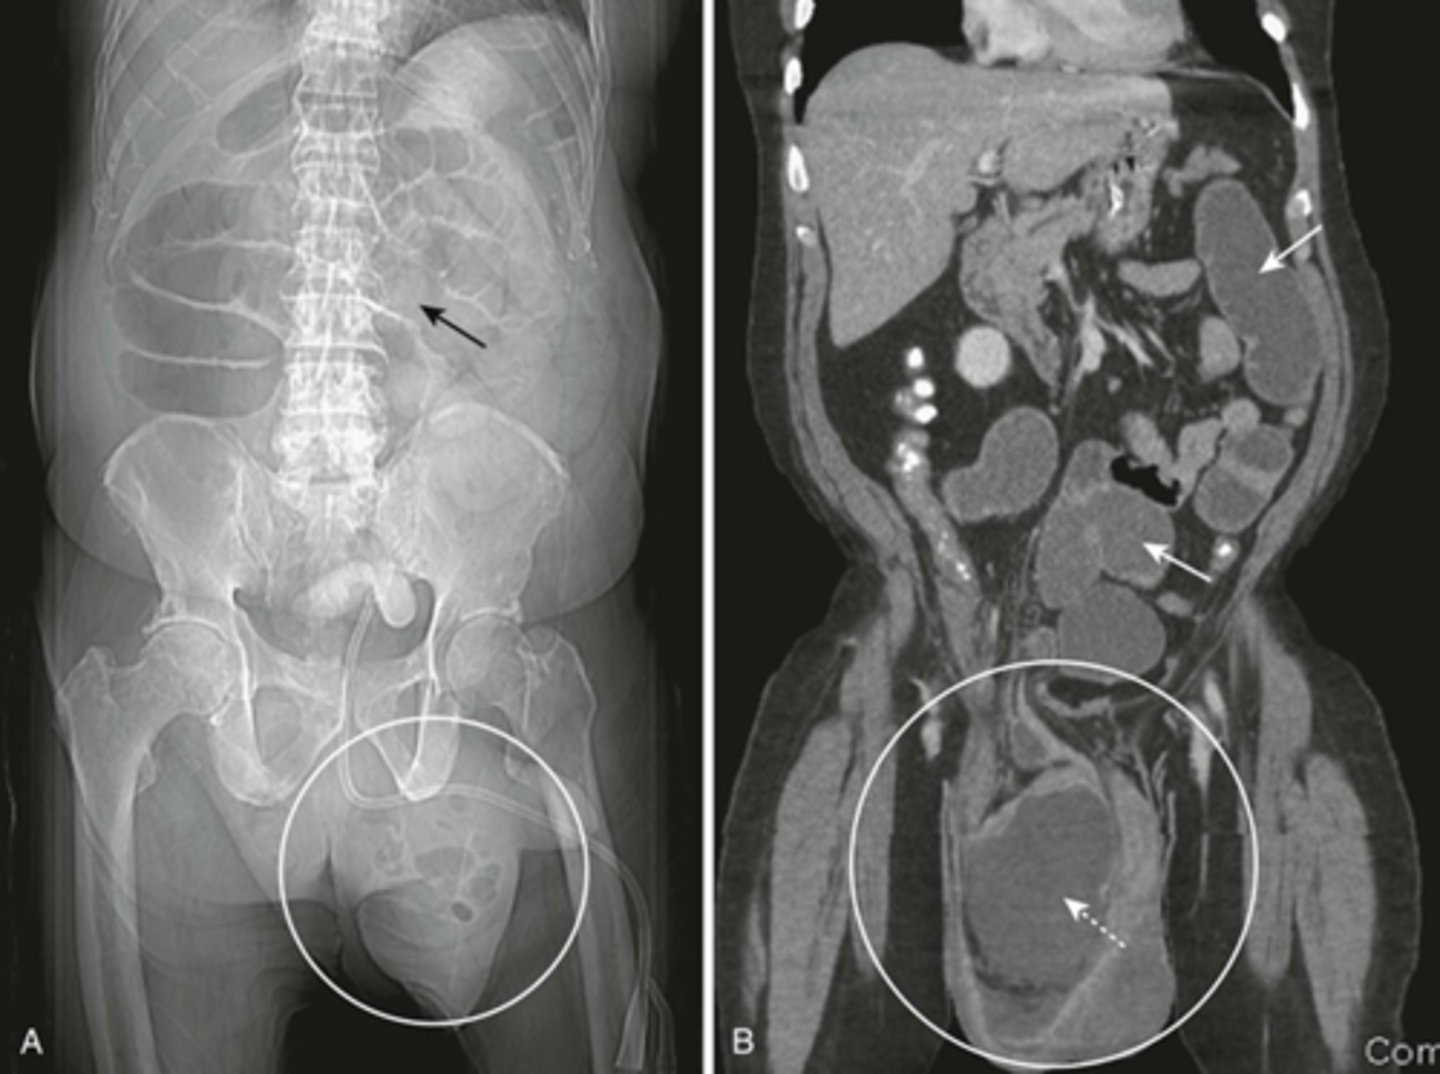

SBO from inguinal hernia.

A:

SOLID BLACK ARROW: dilated loops of small bowel, caused by left inguinal hernia

WHITE CIRCLE: left inguinal hernia.

Loops of bowel should not normally be in the scrotum.

B:

SOLID WHITE ARROWS: multiple fluid-filled and dilated loops of Small bowel, from inguinial hernia

WHITE CIRCLE: inguinal hernia

DOTTED WHITE ARROW: dilated loop of small bowel in inguinal hernia